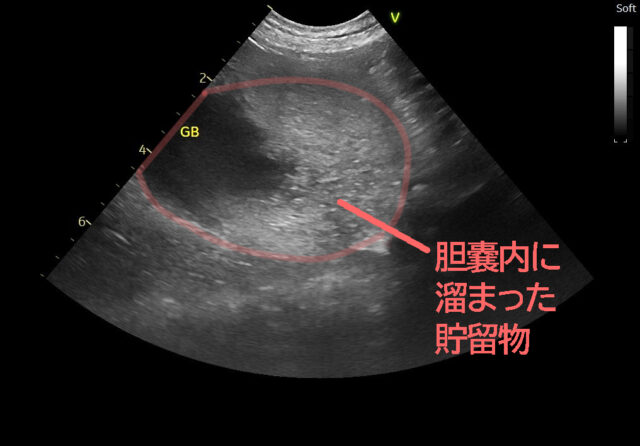

さらに超音波検査を行うと、下の画像のように、胆嚢は拡張し、内部の胆汁は濃く見える像が確認されました。

胆嚢穿刺(エコーガイド下での胆汁採取)を行い、採取した胆汁を培養検査に提出したところ、大腸菌(E. coli)が検出されました。このことから、大腸菌による細菌性胆嚢炎であることが明らかになりました。